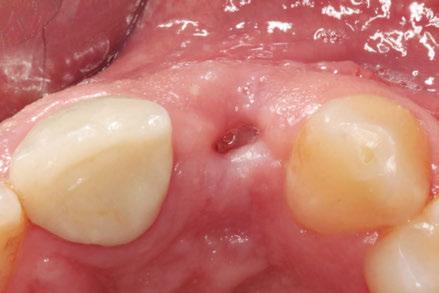

–Implante inmediato en incisivo lateral superior con técnica de «Socket Shield» y acceso vestibular para legrado de la lesión periapical, por el Dr. Ignacio Tormo Jiménez y cols. [106]